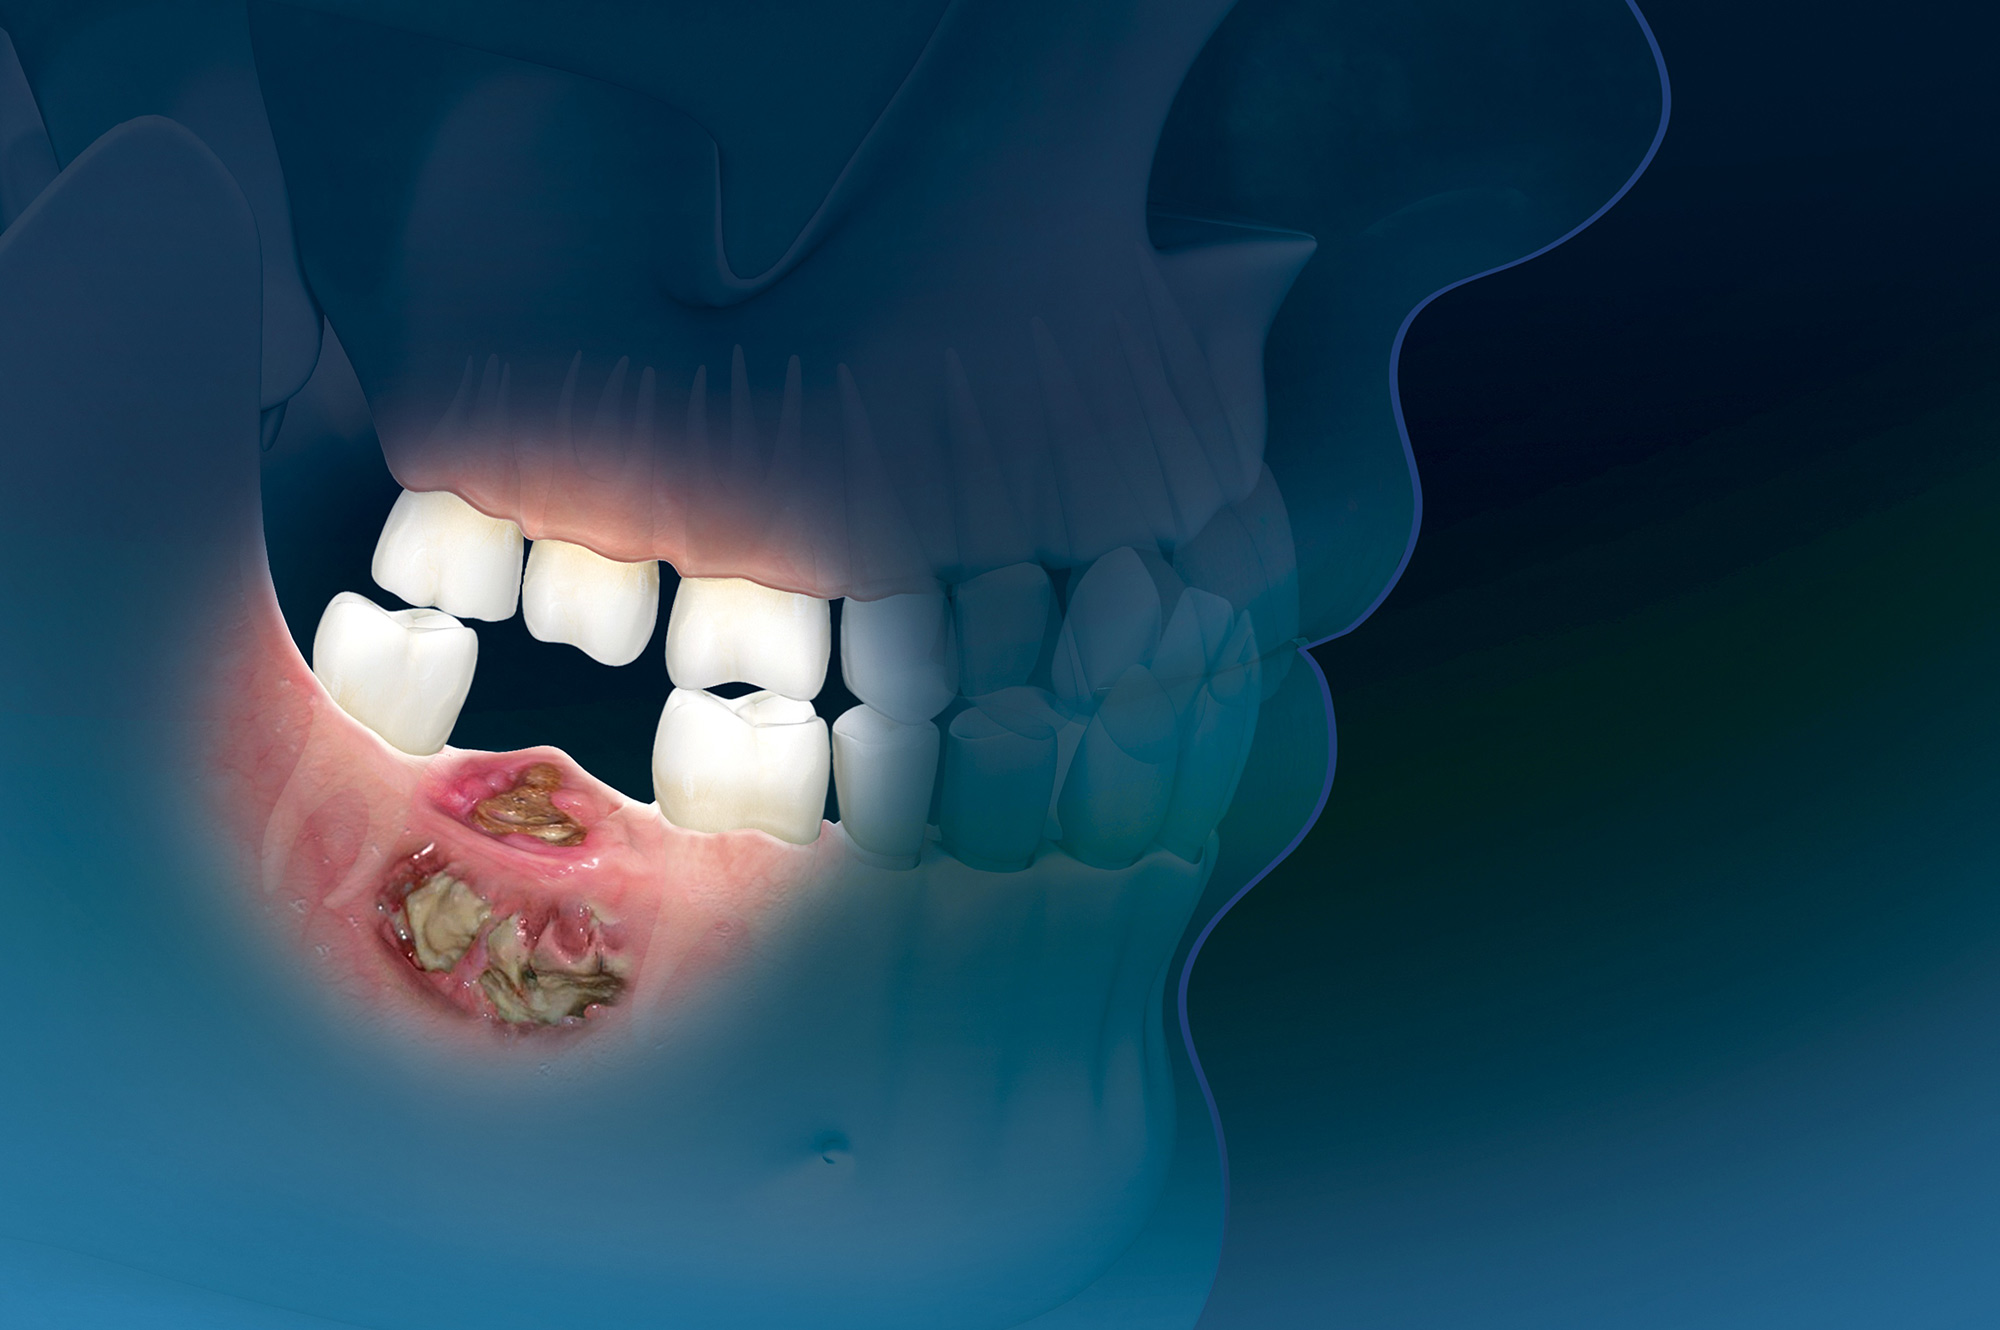

Zoledronato y osteonecrosis de la mandíbula en la osteoporosis: incidencia y factores de riesgo. Análisis de la base de datos francesa de farmacovigilancia

En un entorno de la vida real, nuestros datos confirman que la osteonecrosis de la mandíbula relacionada con bifosfonatos, asociada al zoledronato en la osteoporosis es inusual, aunque ligeramente más común en comparación con los bifosfonatos orales. También creamos conciencia sobre las pautas de cuidado dental y una mayor vigilancia al usar bifosfonatos en pacientes con exposición previa a denosumab. Joint Bone Spine, 2 de junio de 2023

Osteonecrosis de la mandíbula relacionada con la medicación: análisis de la gama de fármacos implicados de la base de datos australiana de notificaciones de eventos adversos

Este estudio contribuye a la escasa pero creciente literatura que asocia un número creciente de fármacos con osteonecrosis de la mandíbula relacionada con la medicación (ONMRM)  y subraya la importancia de considerar todos los fármacos posibles que elevan el riesgo de ONMRM de un paciente. Br J Clin Pharmacol, junio de 2021